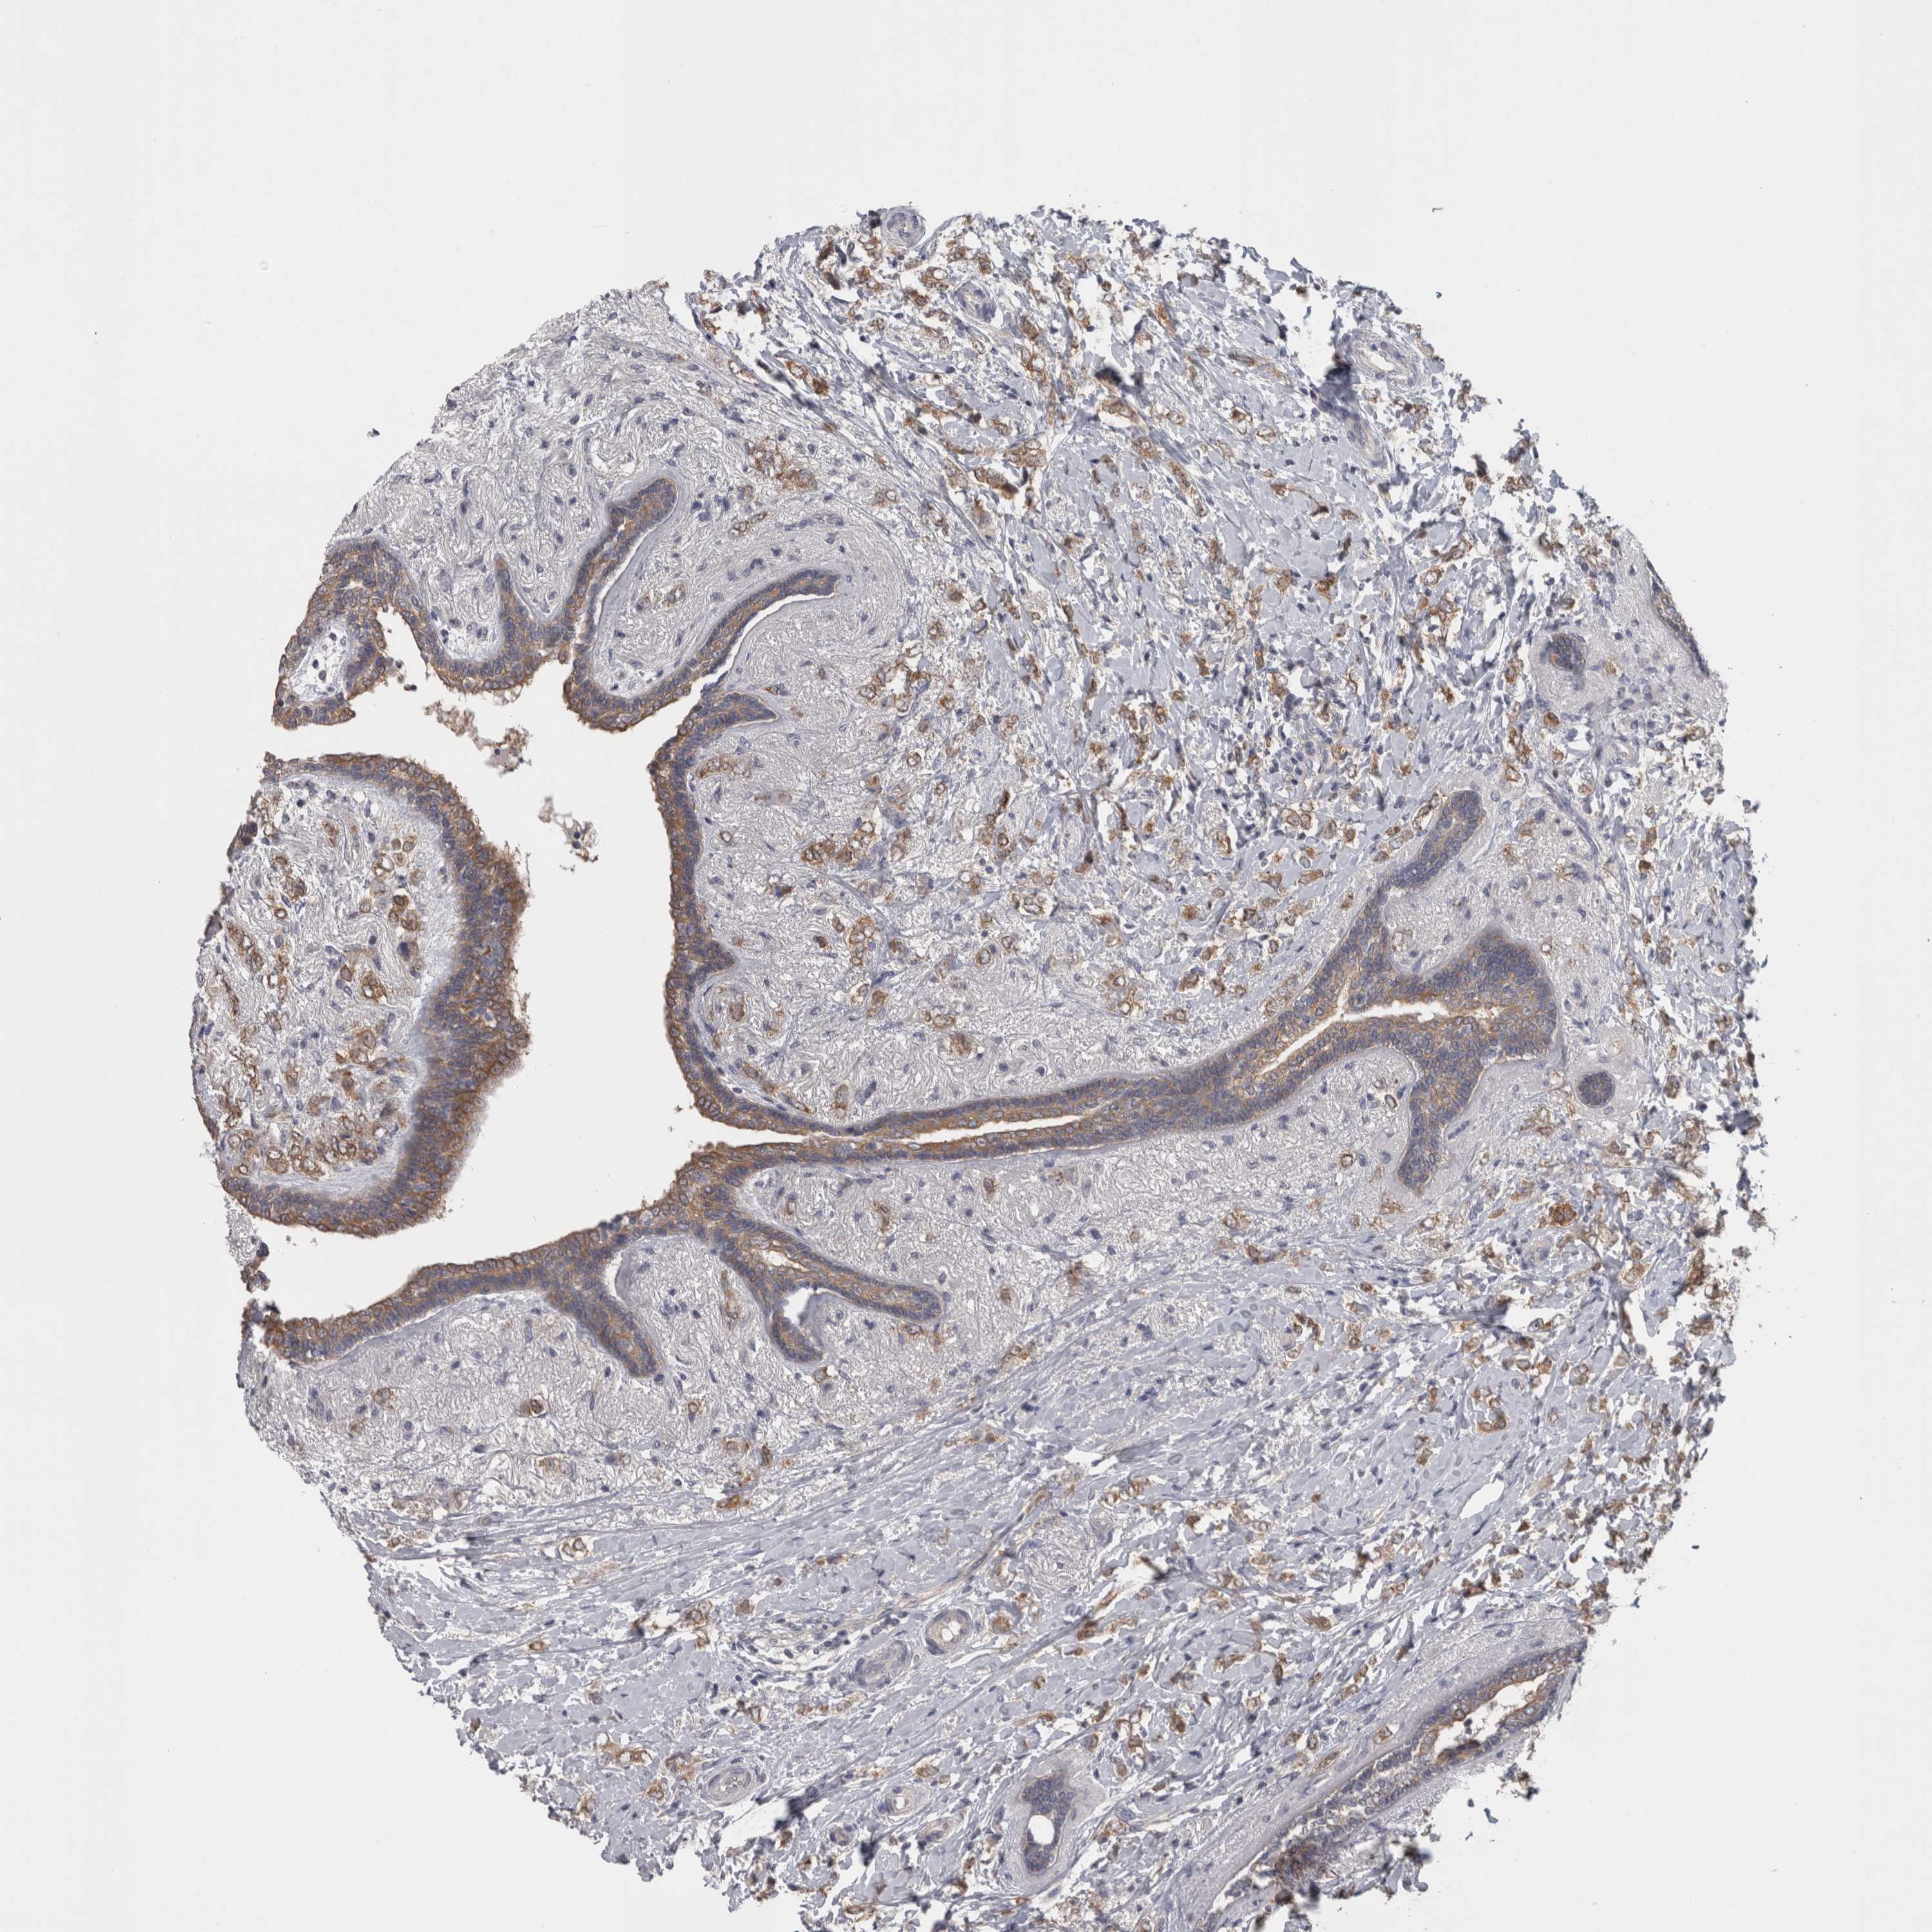

CANCER BREAST CANCER Show tissue menu

BRCA TCGA BRCA VALIDATION PROTEIN EXPRESSION